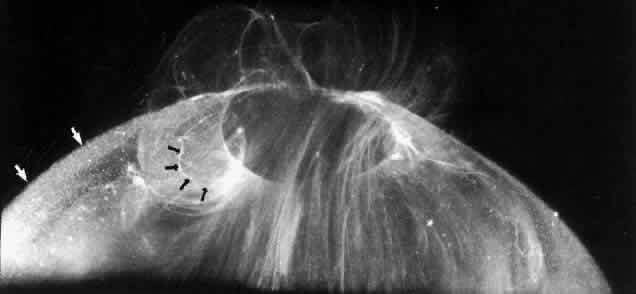

The posterior vitreous cortex is 100-110 μm thick50,60 and, as shown in Figure 12, consists of densely packed collagen fibrils.50,60,152 There is no vitreous cortex over the optic disc (see Figs. 4A AND 13), AND the cortex is thin over the macula due to rarefaction of the collagen fibrils.50 The prepapillary hole in the vitreous cortex can sometimes be visualized clinically when the posterior vitreous is detached from the retina (Fig. 14). If peripapillary glial tissue is torn away during PVD and remains attached to the vitreous cortex about the prepapillary hole it is referred to as Vogt's or Weiss's ring. Vitreous can extrude through the prepapillary hole in the vitreous cortex (see Fig. 4A) but does so to a much lesser extent than through the premacular vitreous cortex (see Figs. 4B AND D and 13). Jaffe153 has described how vitreous can extrude into the retrocortical space created after PVD and has proposed that persistent attachment to the macula (Fig. 15) can produce traction and certain forms of maculopathy.154,155 Although there are no direct connections between the posterior vitreous and the retina, the posterior vitreous cortex is adherent to the internal limiting lamina of the retina, which is actually the basal lamina of retinal Müller cells. The exact nature of the adhesion between the posterior vitreous cortex and the internal limiting lamina is not known but probably results from the presence of various extracellular matrix molecules.91 This concept is supported by studies156,157 in which vitreous cortex separation from the retina was induced using agents that acted on extracellular matrix components that could bind the posterior vitreous cortex to the internal limiting lamina of the retina.

Fig. 13. Posterior vitreous in the left eye of a 59-year-old man. The vitreous cortex (white arrows) envelopes the corpus vitreous and contains multiple, small, highly refractile points that scatter light intensely, which are cells known as hyalocytes. There is a “hole” (black arrows) in the prepapillary posterior vitreous cortex through which vitreous extrudes into the retrocortical space. Larger amounts of vitreous extrude through the premacular vitreous cortex, and fibers course from the central vitreous into the retrocortical space. (Sebag J, Balazs EA: Human vitreous fibres and vitreoretinal disease. Trans Ophthalmol Soc UK 104:123, 1985)